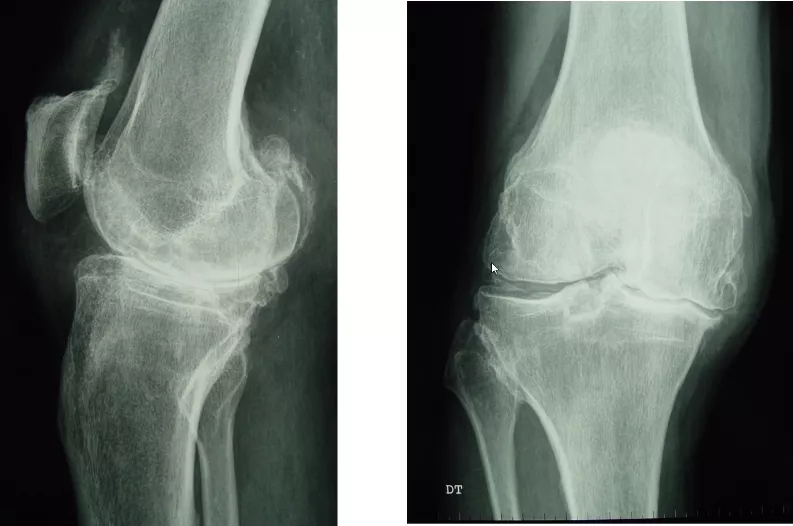

患者情况:女,70岁,主诉:双膝关节疼痛6年,加重伴畸形2年。现病史:患者6年前无明显原因出现双膝关节疼痛,活动后加重,休息可缓解,对症治疗。近2年来,双膝部疼痛及畸形逐渐加重,活动受限。专科情况:双膝关节轻度肿胀,浮髌试验阳性,膝内侧压痛,内外翻应力试验阴性。左膝内翻15°,伸15°-屈110°;右膝内翻10°-屈110°。双下肢肢端感觉血运活动尚可,双手指间关节明显变形。

孙永强教授和袁振教授就胫骨骨缺损处理、假体选择时是否应使用延长杆、术中应使用双侧同期还是双侧分期更好等问题进行了倾囊相授,并给予手术治疗上的建议。随后由山东省邹城市人民医院纪建军主任带来第二则病例分享。患者情况:中年女性,有高血压、糖尿病既往史,因左膝外伤后疼痛、活动受限1年入院。查体:左膝轻度外翻畸形,无明显肿胀,皮肤无红肿、破溃,左膝外侧压痛明显,髌骨研磨试验(+),侧方应力试验(-),膝关节活动范围约为0°-120°,足趾感觉及血运正常。入院诊断:1.左膝创伤性关节炎;2.左胫骨平台陈旧性骨折;3.高血压病;4.糖尿病;5.骨质疏松症。